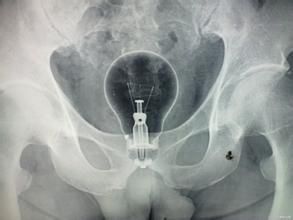

多數病例可以單純根據病史獲得診斷,孩子的家長常能訴說孩子口裡含弄的某物突然失蹤;較大的兒童還能清楚地說出口中含著某物,因某種情況而使他把異物吞入胃中。吞入的異物如不發生阻塞或穿破等併發症,常無明確的體徵可以作為診斷的依據而最後的診斷常需通過X線檢查方能確定包括異物的大小形態、所在的部位、有無自行通過的可能及可能被嵌住的部位等。

1.X線腹部平片純金屬異物經X線檢查,可得到肯定性診斷。2.鋇餐造影非金屬異物透過吞鋇造影很有幫助如有出血或穿孔,則禁行鋇餐檢查。